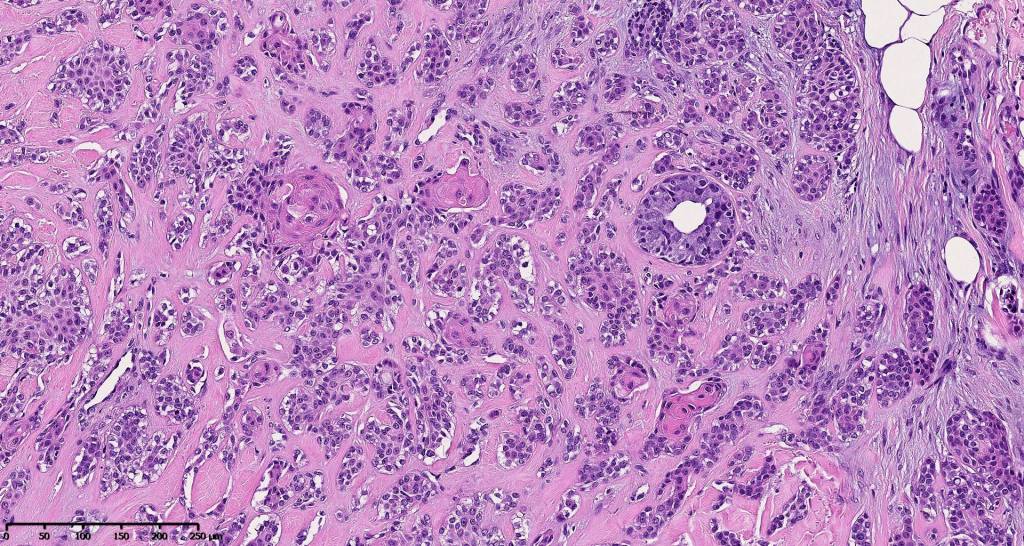

•Well circumscribed unencapsulated, nodular/multinodular silhouette composed of an admixture of epithelial & mesenchymal elements

•Mixed epithelial component including nests & cords of epithelium with abundant, eosinophilic cytoplasm & small vesicular nuclei

•Glandular differentiation sometimes showing apocrine differentiation

•Cribriform/retiform appearance occasionally evident

•Stromal sclerosis & hyalinization

•Myxoid change

•Chondroid foci